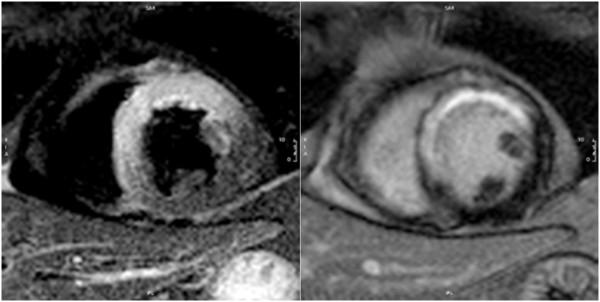

Standardized image interpretation and post processing in cardiovascular magnetic resonance: Society for Cardiovascular Magnetic Resonance (SCMR) board of trustees task force on standardized post processing.

With mounting data on its accuracy and prognostic value, cardiovascular magnetic resonance (CMR) is becoming an increasingly important diagnostic tool with growing utility in clinical routine. Given its versatility and wide range of quantitative parameters, however, agreement on specific standards for the interpretation and post-processing of CMR studies is required to ensure consistent quality and reproducibility of CMR reports. This document addresses this need by providing consensus recommendations developed by the Task Force for Post Processing of the Society for Cardiovascular MR (SCMR). The aim of the task force is to recommend requirements and standards for image interpretation and post processing enabling qualitative and quantitative evaluation of CMR images. Furthermore, pitfalls of CMR image analysis are discussed where appropriate.